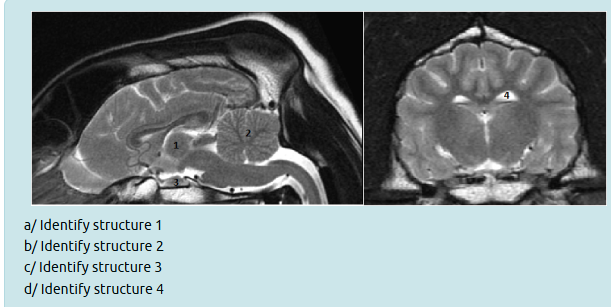

Interthalamic adhesion

Cerebellum

Pituitary gland

Lateral ventricle